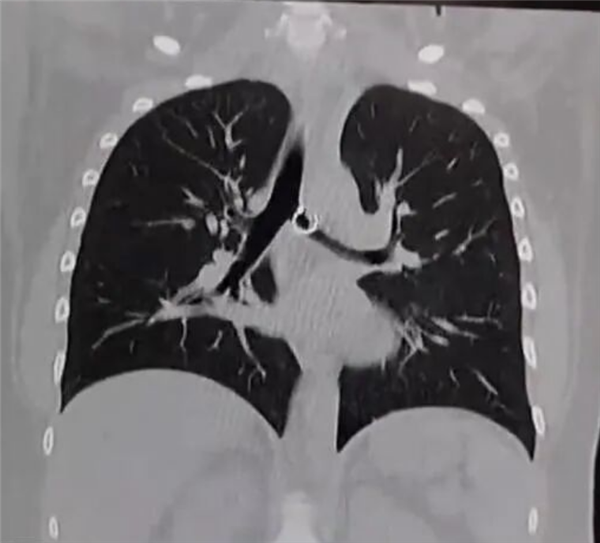

直到咳嗽持续一个月,甚至影响正常生活,她才就医检查,X光和CT扫描清晰显示,其肺部有一枚金属异物,正是她丢失的鼻环。

医生检查后直言情况极度危险,鼻环已深深嵌入肺部组织,一端的金属小球距离肺主动脉仅0.5毫米,一旦移位或被触碰,就可能刺破主动脉,导致瞬间大出血,几乎没有抢救时间。